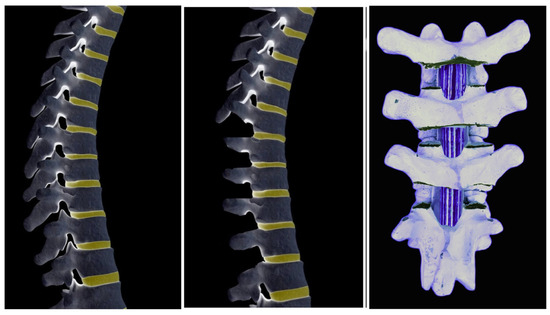

7. Posterior Release

8. Temporary Internal Distraction Rods

9. MCGR as Temporary Internal Traction